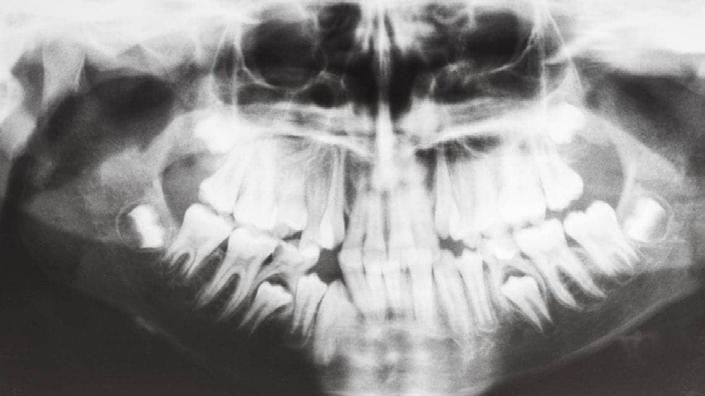

Stanford researchers say the shrinking of the human jaw is due to lifestyle factors rather than species evolution

AHIDDEN EPIDEMIC OF SHRINKING JAWS IS BEHIND MANY ORTHODONTIC AND HEALTH ISSUES, STANFORD RESEARCHERS SAY.

The shrinking of the human jaw in modern humans is not due to genetics but is a lifestyle disease that can be proactively addressed, according to Stanford researchers.

For many of us, orthodontic work – getting fitted with braces, wearing retainers – was just a late-childhood rite of passage. The same went for the pulling of wisdom teeth in early adulthood. Other common conditions, including jaw pain and obstructed sleep apnea – when slack throat muscles interrupt breathing during rest –also just seem like par for the course.

The broader scientific community has largely deemed the underlying abnormality behind these problems as hereditary

and untreatable, and opted to deal with symptoms through medical devices and after-the-fact interventions.

But in a new study, Stanford researchers and colleagues argue that all these issues and more are actually relatively new problems afflicting modern humans and can be traced to a shrinking of our jaws. Moreover, they maintain that this “jaws epidemic” is not primarily genetic in origin, as previously thought, but rather a lifestyle disease. That means the epidemic is largely the result of human practices and akin to obesity, type 2 diabetes, heart disease and some cancers.

The study – published in the journal BioScience – marshals the growing evidence from studies conducted around the world surrounding the jaws epidemic, as well as how to address it proactively. Parents and caregivers can take steps to promote proper mouth, jawbone and facial musculature development in children, the study advises, to help stave off future

health burdens and chronic conditions.

“The jaws epidemic is very serious, but the good news is, we can actually do something about it,” said Paul Ehrlich, the Bing Professor of Population Studies, Emeritus, at Stanford and one of the study’s authors.

The new study builds upon a book Ehrlich co-wrote with orthodontist and lead study author Sandra Kahn entitled Jaws: The Story of a Hidden Epidemic, published by Stanford University Press in 2018. Two other Stanford researchers, Robert Sapolsky and Marcus Feldman, have contributed their expertise to the new study. Seng-Mun “Simon” Wong, a general dentist in private practice in Australia, was also a co-author.

Anthropologists have long noted the significant differences between the jaws and teeth in modern skulls compared to

BY GEOFFREY MONTES / SPECIAL TO POLO LIFESTYLES

pre-agricultural, hunter-gatherer humans from thousands of years ago. The differences are stark even compared to humans who lived as recently as a century-anda-half ago during pre-industrial times. These bygone humans showed little teeth crowding, impaction of their wisdom teeth (a leading reason for their surgical removal nowadays) or malocclusion – the abnormal positioning of the upper and lower teeth when the mouth is closed.

Assuming that genetics are chiefly responsible for the sudden modern rise of these dental maladies does not make sense, said Ehrlich. “There’s not been enough time for evolution over the span of only several generations to have made our jaws shrink,” said Ehrlich. Nor is there any evidence of selection pressures that would have favored smaller jawed-people producing more offspring – and thus perpetuating the trait – than regular-jawed people.

“The evidence of a genetic contribution

to the jaws epidemic is not strong,” said Feldman, who is a population geneticist and the Burnet C. and Mildred Finley Wohlford Professor and professor of biology.

Instead, profound physiological changes can occur in human populations over short intervals, Feldman pointed out, purely as a result of environmental factors, such as dietary choices and cultural norms. For instance, since World War II, a switchover from heavy rice consumption to more dairy and protein in childhood has been linked to Japanese men gaining around 5 inches in average adult height.